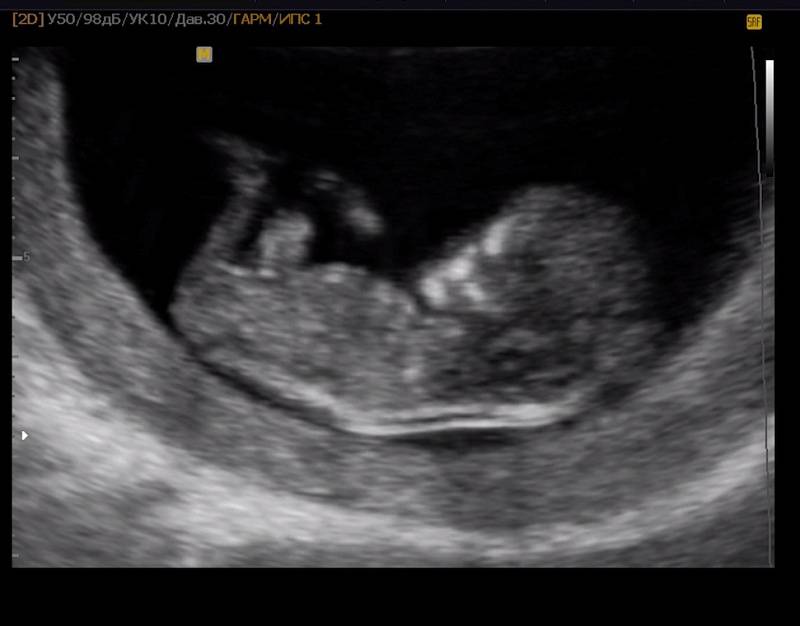

Буква D обозначает слово Dimension – «измерение». Когда мы слышим слово ультразвук, то обычно всем на ум приходит такая черно-белая картинка. Это как раз то, что принято называть 2D. Можно сказать, что это стандартный режим от которого отталкиваются все остальные режимы? и какое исследование вы бы вначале не выбрали, в любом случае, в этом режиме пройдет большая его часть. Большинство параметров оцениваются именно в нем, такие как: измерение размеров плода, оценка строения головного мозга, внутренних органов и даже оценка работы сердца в реальном времени. Обычно это не самый интересный для “непосвещенных” режим, но в определенных плоскостях, картинка может быть достаточно понятной любому.

Сопоставьте: слева УЗИ 2d, а с правой стороны 3d